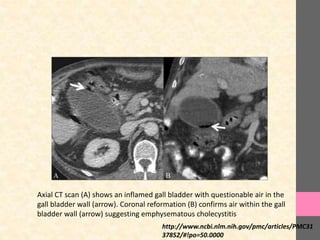

Axial CT scan (A) shows an inflamed gall bladder with questionable air in the

gall bladder wall (arrow). Coronal reformation (B) confirms air within the gall

bladder wall (arrow) suggesting emphysematous cholecystitis

Axial CT scan(A) shows an inflamed gall bladder with questionable air in the gall bladder wall (arrow). Coronal reformation (B) confirms air within the gall bladder wall (arrow) suggesting emphysematous cholecystitis http://www.ncbi.nlm.nih.gov/pmc/articles/PMC31 37852/#!po=50.0000